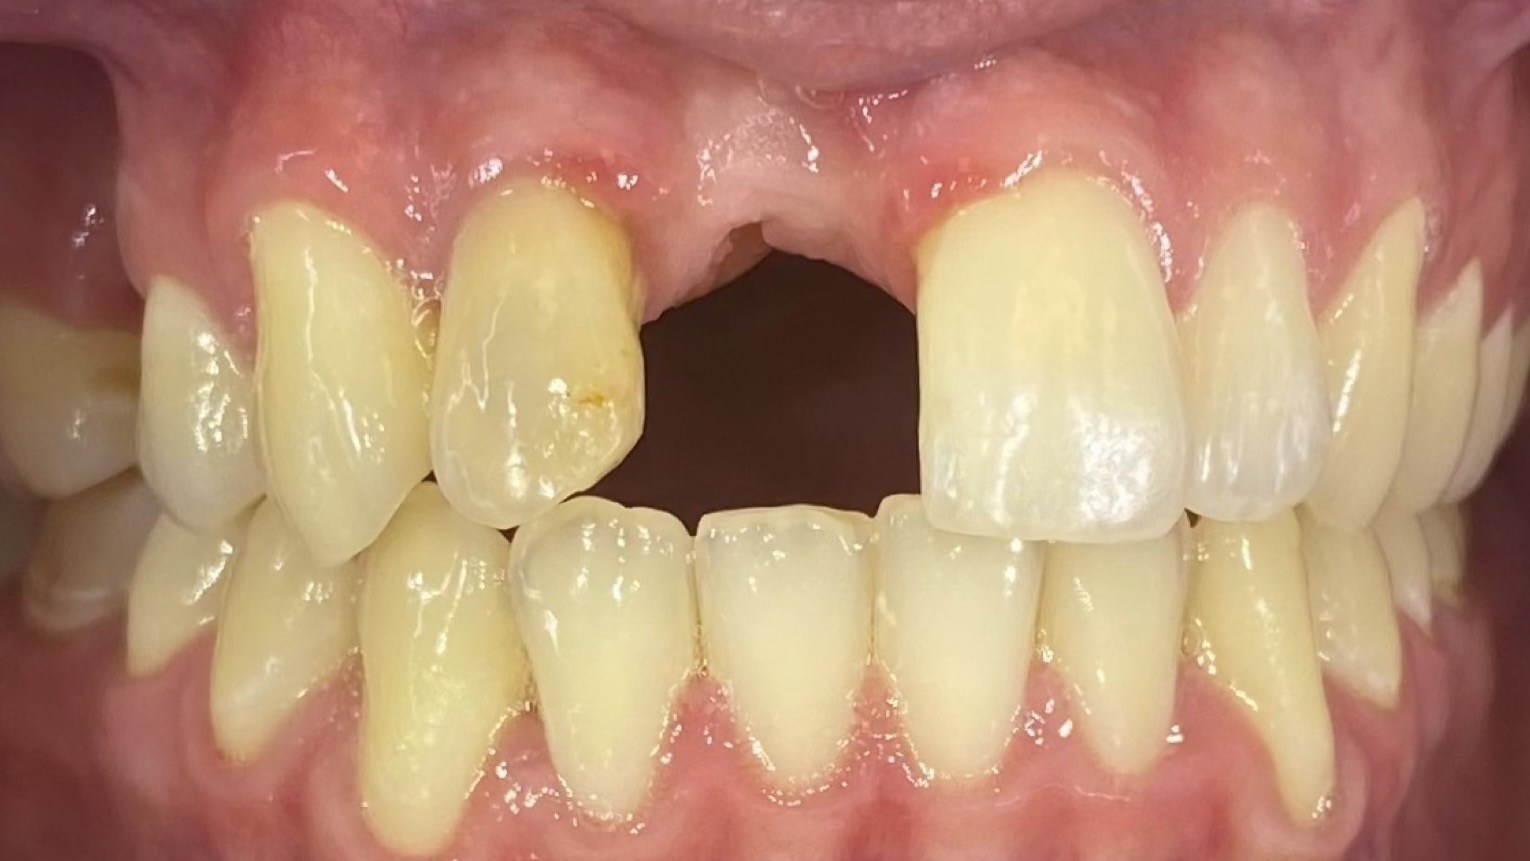

The poster provided a clear and structured overview of the pre-, intra-, and postoperative stages of ceramic implant placement, illustrating:

the biological reasoning behind treatment decisions,

the dynamics of soft- and hard-tissue healing,

and the long-term functional and aesthetic outcomes achievable with ceramic implants.